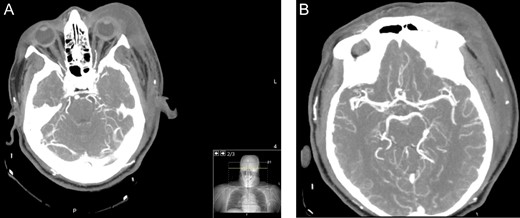

A 60-year-old male with a past medical history of hypertension presented to the emergency department of a District General Hospital with a 7-day history of a worsening left eye swelling, pain and erythema. There was no history of previous trauma, sinus disease or recent surgery. On arrival, clinical examination revealed that the patient was in circulatory shock with signs of sepsis. Immediate treatment for a suspected septic shock due to left periorbital cellulitis was started with broad-spectrum intravenous (IV) antibiotics (Vancomycin, Gentamycin, Meropenem and Clindamycin), aggressive fluid resuscitation and oxygen supplementation. A computed tomography (CT) carotid angiogram revealed a diffuse left orbital cellulitis with no intraorbital collection (Fig. 1A). There was no evidence of intracerebral vascular thrombosis (Fig. 1B). Blood tests showed an inflammatory picture (Table 1).

Axial CT angiogram carotids images showing (A) diffuse left periorbital region involvement with no retro-orbital or extra-orbital collections. (B) No evidence of vessel thrombosis.